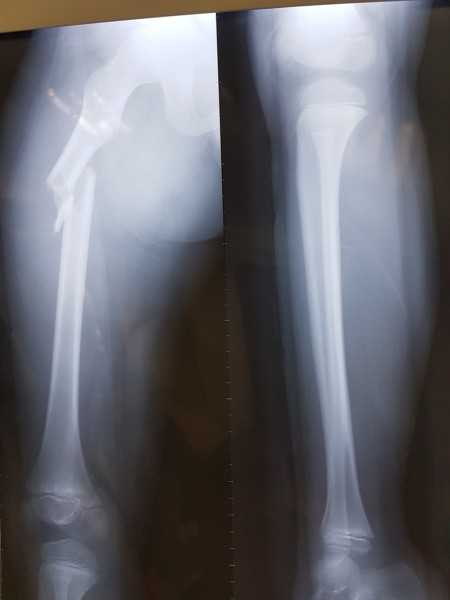

Đến nơi, gia đình được bác sĩ chẩn đoán cháu bị gãy xương đùi phải. Ngày 3/12, cháu Kiên phải mổ để nẹp vít xương do ca gãy chân quá nặng, không thể bó bột.

Vết gãy đôi xương đùi của cháu Trần Chí Kiên. Ảnh phụ huynh cung cấp